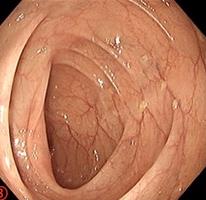

• 利那洛肽联合西甲硅油与复方聚乙二醇电解质散对便秘患者肠道清洁效果的影响

2025, 31(6):44-53. DOI: 10.12235/E20240604

摘要:目的 探讨利那洛肽联合西甲硅油与复方聚乙二醇电解质散(PEG)对便秘患者肠道清洁效果的有效性和安全性。方法 采用前瞻性随机对照试验,通过单盲法,纳入2023年4月-2024年8月于该院消化内镜中心行结肠镜检查的便秘患者383例,随机分为常规组(128例)、实验A组(128例)和实验B组(127例)。常规组采用3 L PEG(Ⅰ)溶液,实验A组采用290 μg利那洛肽 + 2 L PEG溶液,实验B组采用290 μg利那洛肽 + 30 mL西甲硅油+2 L PEG溶液。比较3组患者的肠道准备效果[Boston肠道准备量表(BBPS)评分和去泡效果]、病变检出率、首次排便间隔时间、排便次数、盲肠插管成功率、进镜时间、退镜时间、不良反应发生率和重复检查意愿等。结果 3组患者BBPS评分比较,差异无统计学意义(P > 0.05);实验B组的去泡效果评分明显低于常规组和实验A组,差异均有统计学意义(P < 0.05);实验B组的病变总检出率和息肉检出率明显高于常规组和实验A组,差异均有统计学意义(P < 0.05);常规组的首次排便间隔时间明显长于实验A组和实验B组,差异均有统计学意义(P < 0.05);3组患者排便次数比较,差异无统计学意义(P > 0.05);3组患者盲肠插管成功率均为100.0%,进镜时间相当,差异均无统计学意义(P > 0.05);实验B组的退镜时间明显短于常规组和实验A组,差异均有统计学意义(P < 0.05);常规组腹胀腹痛发生率和不良反应总发生率明显高于实验A组和实验B组,差异均有统计学意义(P < 0.05);常规组重复检查意愿率明显低于实验A组和实验B组,差异均有统计学意义(P < 0.05)。结论 290 μg利那洛肽联合30 mL西甲硅油与2 L PEG溶液方案在便秘患者肠道准备上具有优势,较3 L PEG溶液和290 μg利那洛肽+2 L PEG溶液方案,可获得更好的肠道清洁效果,且安全性和患者重复检查意愿率高,可作为便秘患者肠道准备的推荐方案。